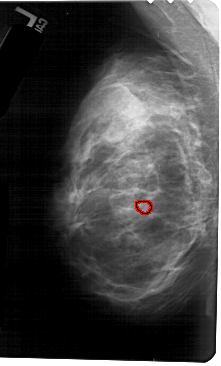

A_1685_1.LEFT_CC

FILE: A_1685_1.LEFT_CC.OVERLAY

TOTAL_ABNORMALITIES 1

ABNORMALITY 1

LESION_TYPE CALCIFICATION TYPE PLEOMORPHIC DISTRIBUTION CLUSTERED

ASSESSMENT 4

SUBTLETY 1

PATHOLOGY BENIGN

TOTAL_OUTLINES 1

BOUNDARY